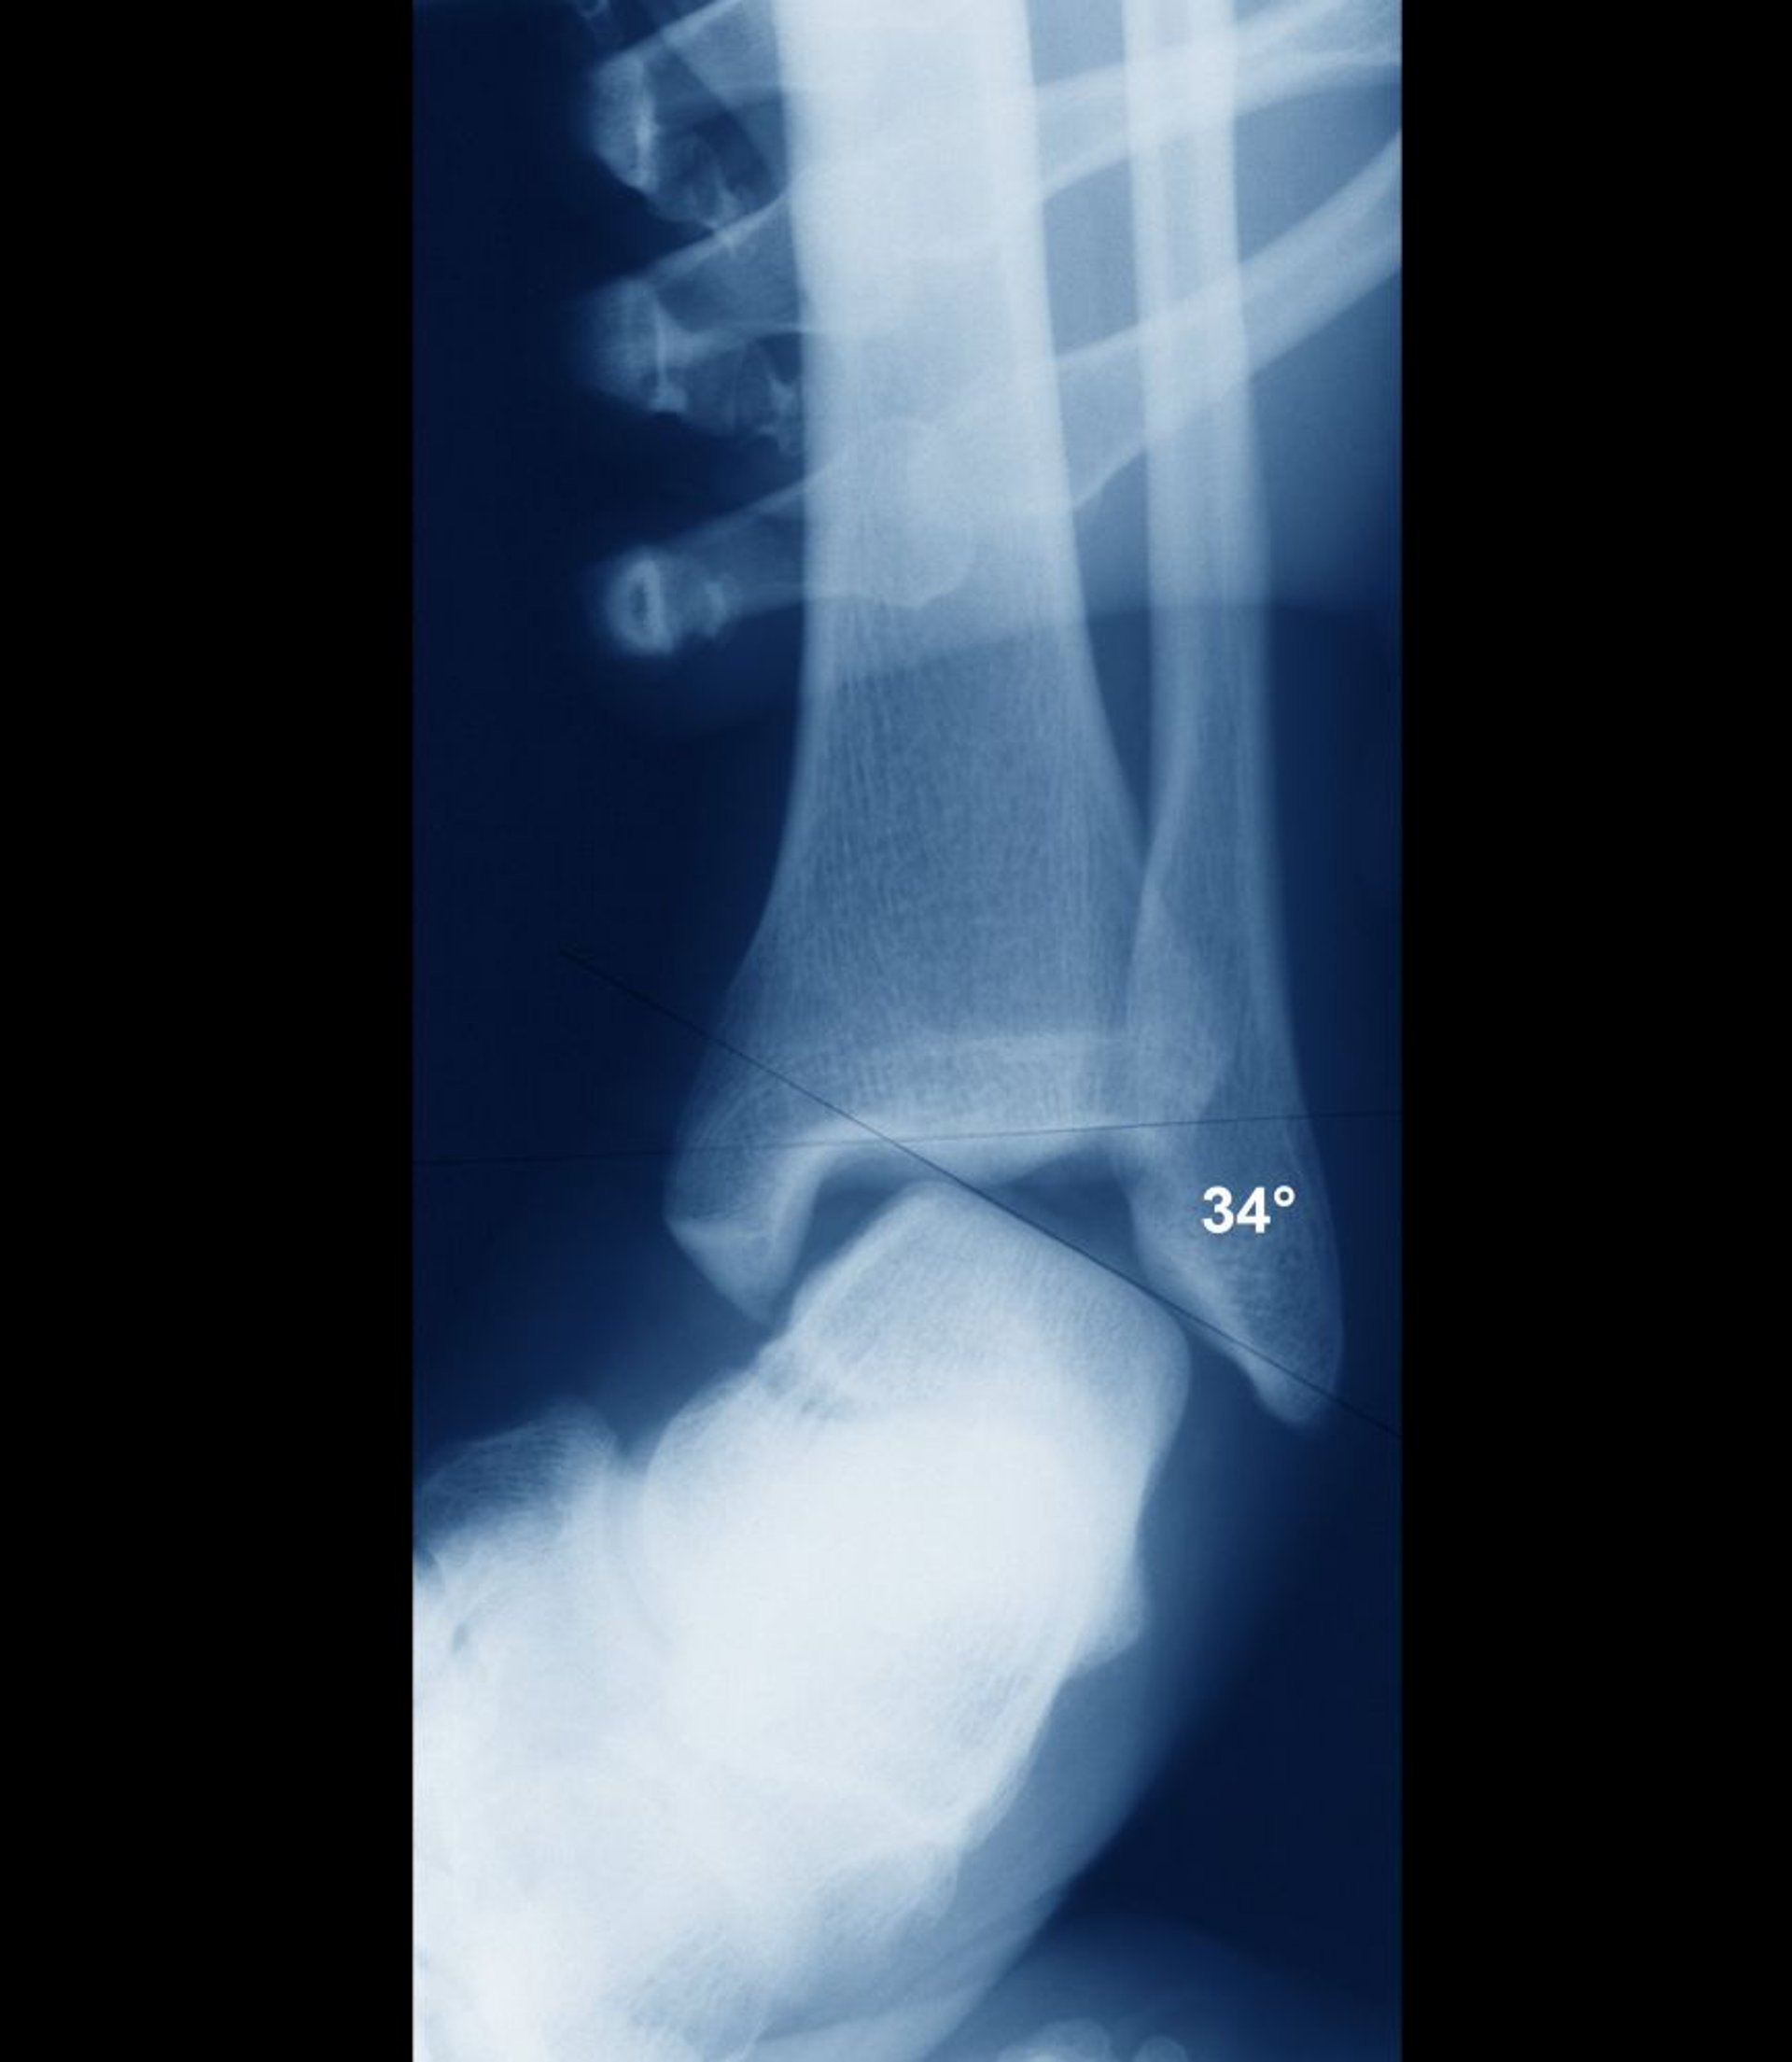

Ankle Sprain With Instability

If the ankle is stable, the intra-articular surfaces of the talus and tibia should be parallel. Here, they are widely misaligned, indicating gross joint instability. Instability would have been clearly evident clinically, and instability is normally assessed clinically without need for radiographs.